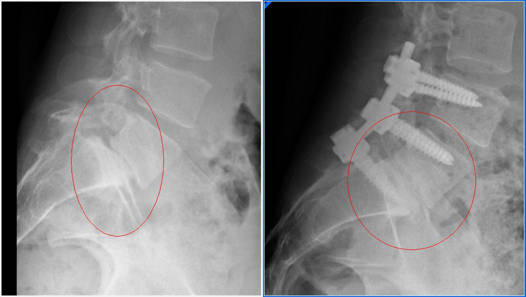

- La artrodesis vertebral es la técnica de elección para el tratamiento de la espondilolistesis, esta técnica consiste en realizar una fusión entre las vértebras para evitar que una se deslice sobre la otra. La artrodesis vertebral se acompaña de una laminectomía para liberar los nervios que puedan estar comprimidos. La artrodesis vertebral es una técnica eficaz, que consigue el alivio del dolor y de la incapacidad.

Existen distintas técnicas quirúrgicas para realizar una fusión vértebral sin embargo ninguna ha demostrado ser más eficaz que otra para resolver los síntomas.

La técnica quirúrgica más utilizada será la fusión cervical principalmente la que se realiza por vía anterior, en los casos de vértebras muy desplazadas o inestables además de la fusión anterior en ocasiones tendremos que realizar una fusión posterior y poner tornillos desde la parte posterior de la vértebra.